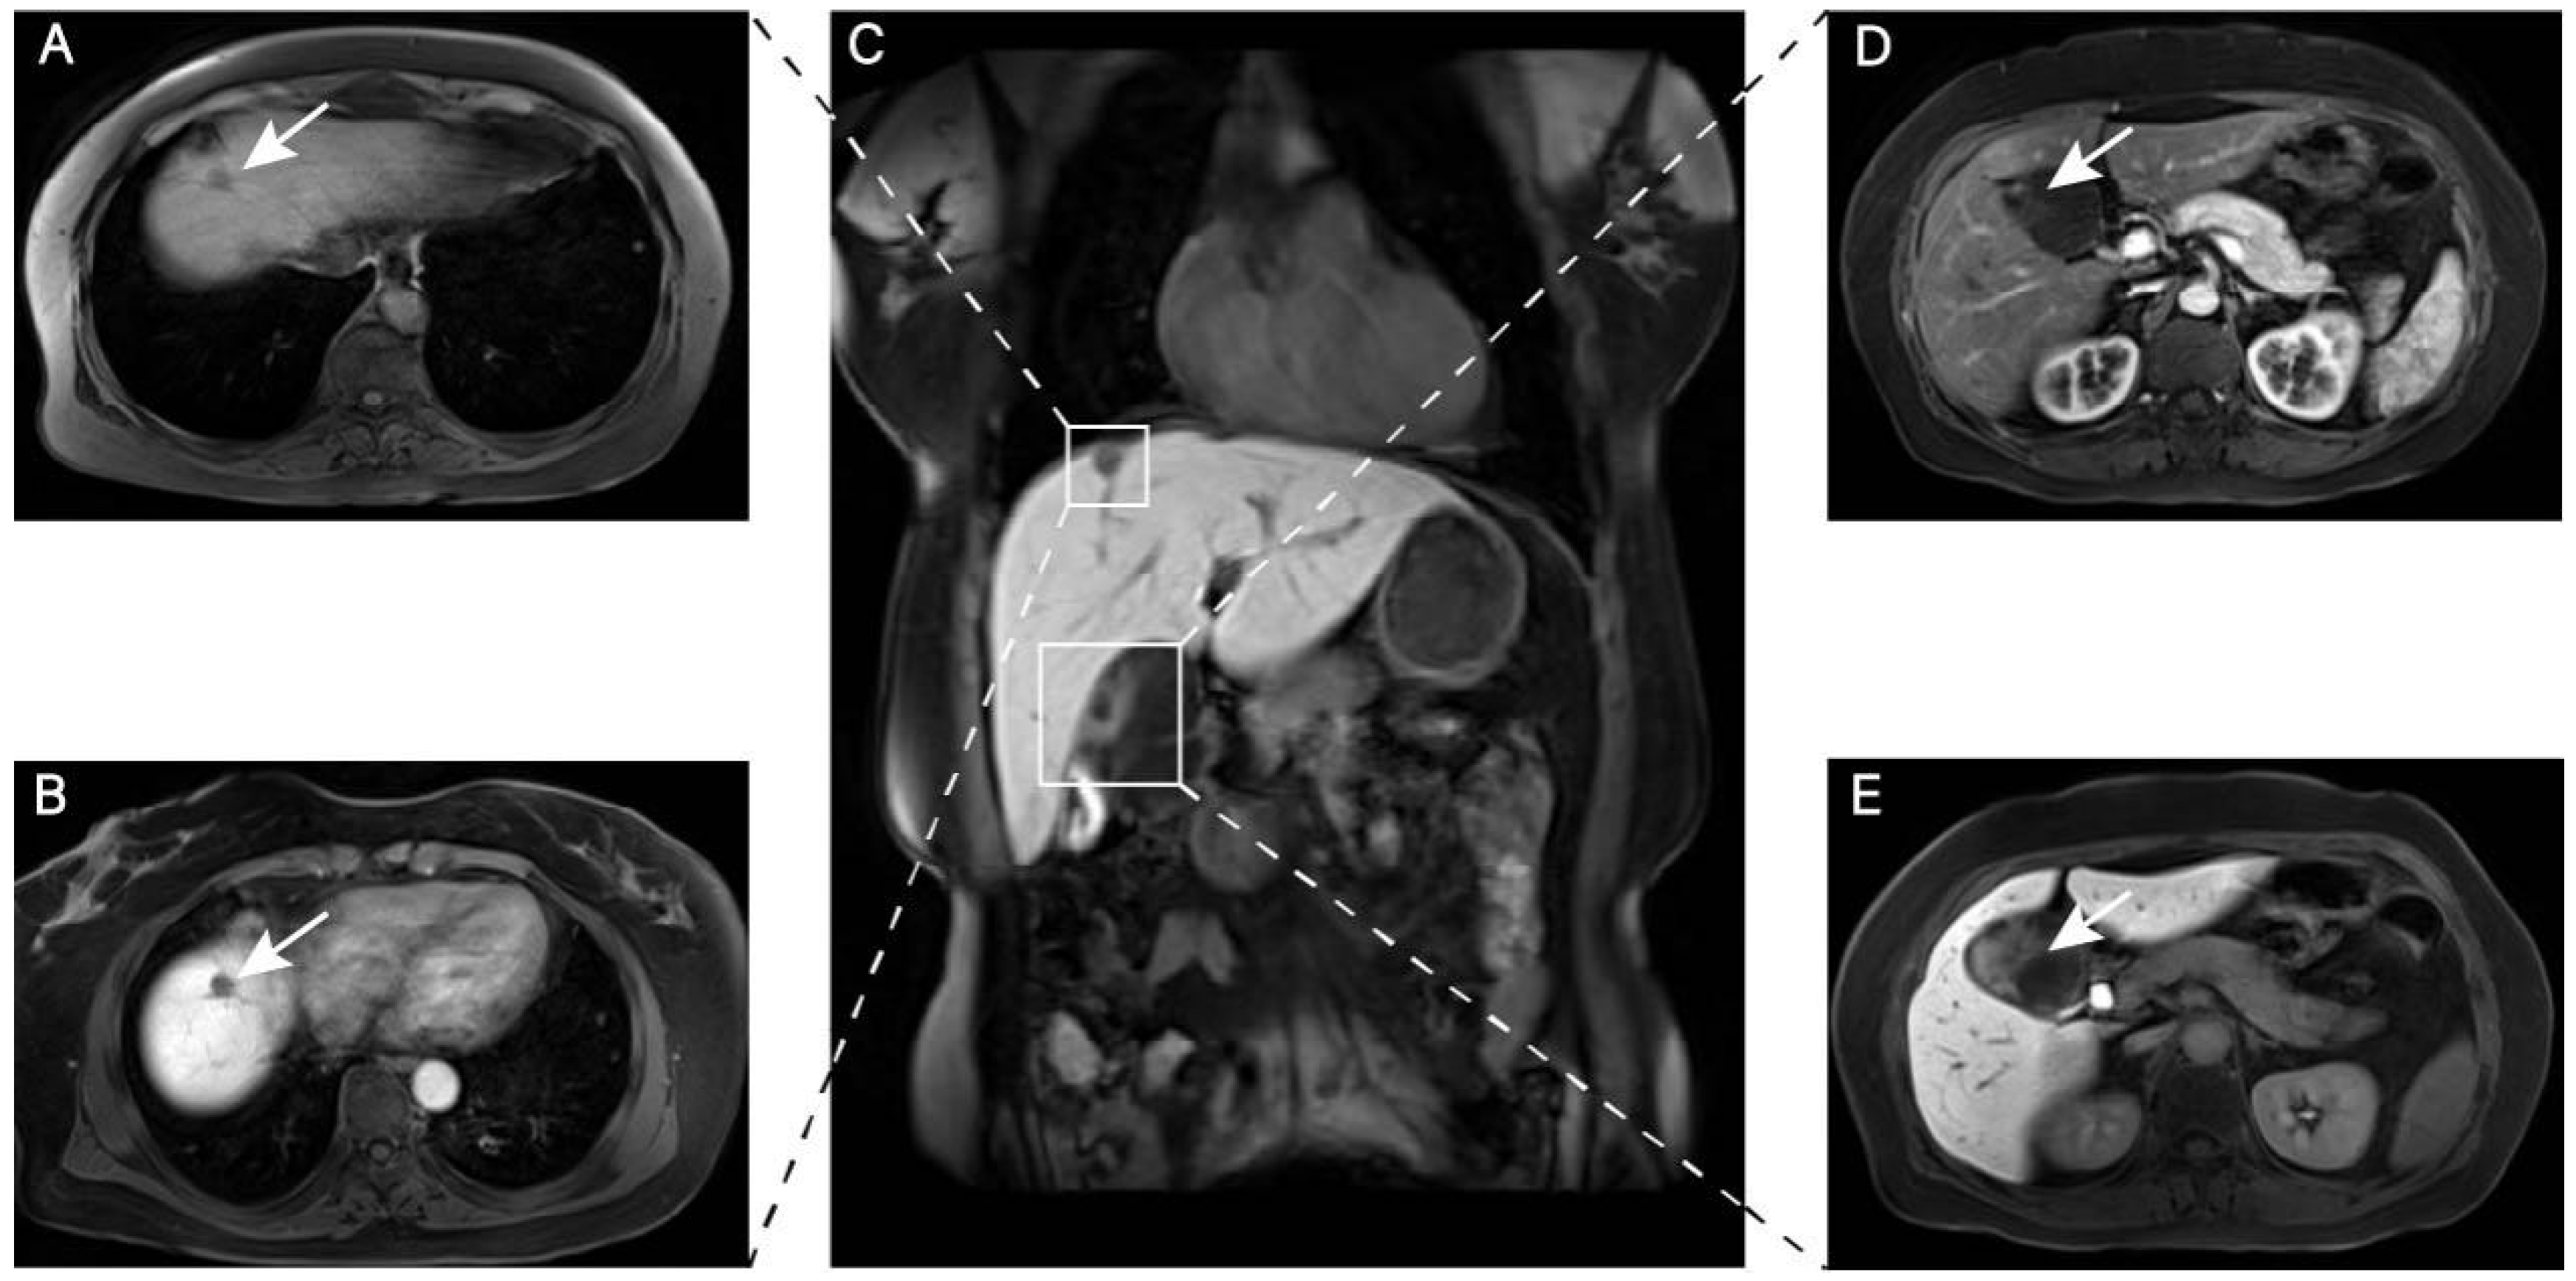

2. Case Report

3.1. Preoperative Differential Diagnosis of HLPD Versus HCC

3.2. Preoperative Differential Diagnosis of Gallbladder Schwannoma Versus Gallbladder Cystadenoma